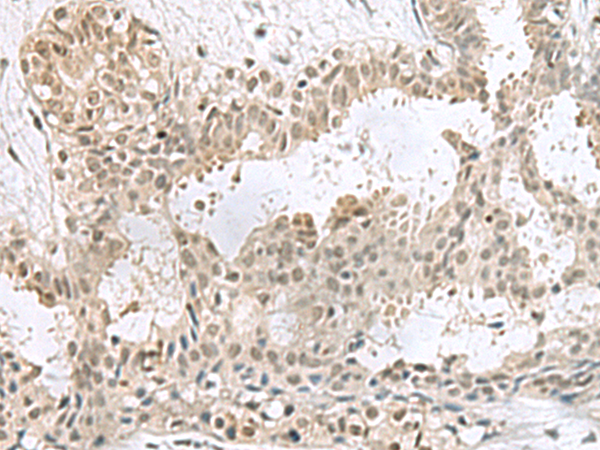

IHC (Immunohistochemisry)

(Immunohistochemistry of paraffin-embedded Human thyroid cancer tissue using PCBD1 Polyclonal Antibody at dilution of 1:60(×200))